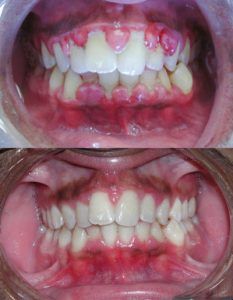

Gengive-infiammateRiconoscere una gengivite non è difficile ma è molto importante perchè come abbiamo accennato prima questa patologia di per sé piuttosto innocua rischia di degenerare in patologie dentali molto più serie. I sintomi più comuni di una gengivite nel suo primo stadio sono i seguenti:

• Sanguinamento delle gengive (soprattutto quando si lavano i denti);

• Alito cattivo;

• Gengive arrossate, gonfie e poco sode;

• Cattivo sapore in bocca.